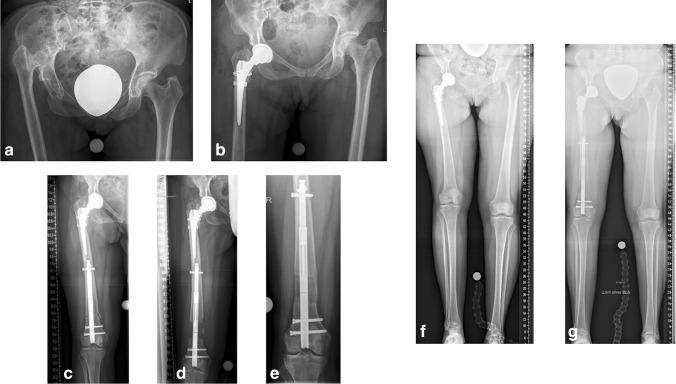

PATIENTS/MATERIAL/METHODS: Retrospective analysis of clinical data and radiographs of five patients (age 38.1 (28-51) years) with unilateral NHD who underwent THA with (n  = 3) or without (n = 2) subtrochanteric shortening osteotomy (SSO) and secondary intramedullary femoral lengthening through a retrograde magnetically-driven lengthening nail (follow-up 18.4 (15-27) months).

LLD was 51.0 (45-60) mm before and 37.0 (30-45) mm after THA. Delayed bone union at one SSO site healed after revision with autologous bone grafting and plate fixation. Subsequent lengthening led to leg length equalisation in all patients. Complete consolidation was documented in all lengthened segments.

Staged reconstruction of unilateral neglected hip dislocation through total hip arthroplasty and subsequent intramedullary femoral lengthening.